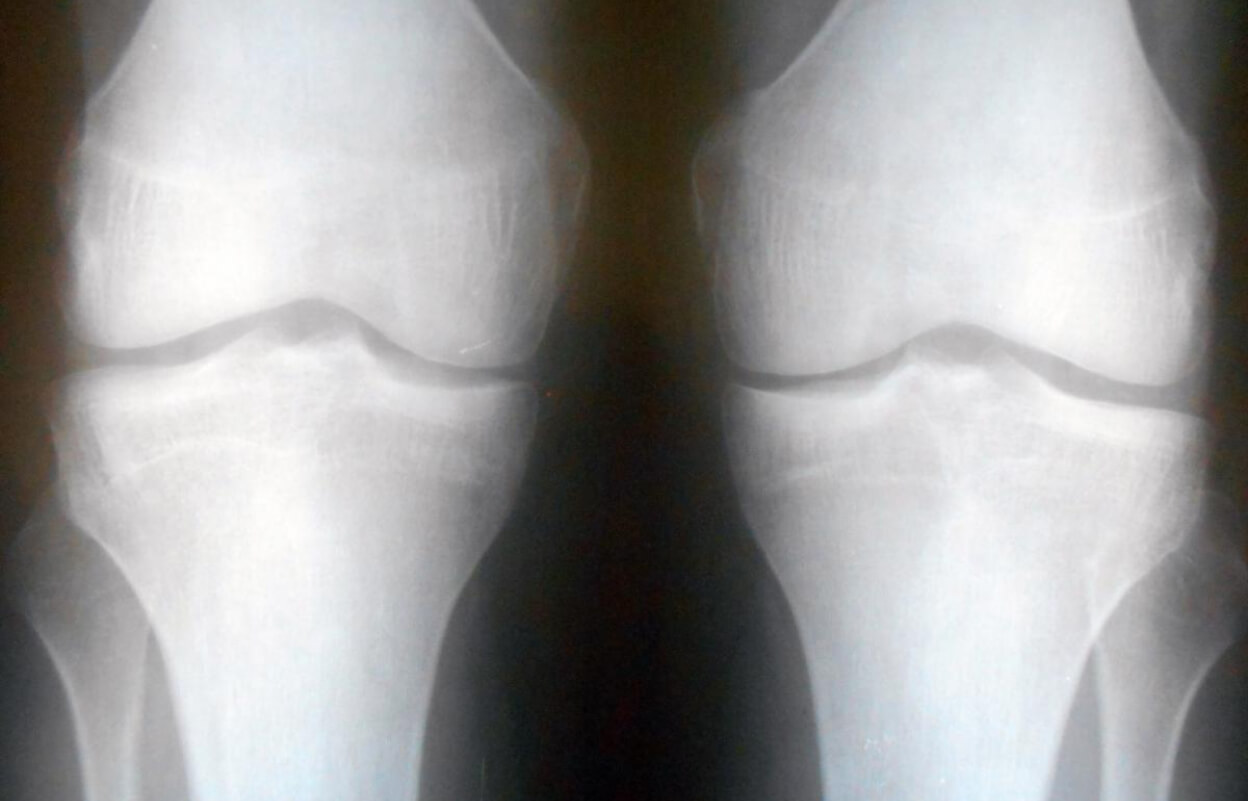

Далее назначают рентгенографию. Рентгеновские снимки показывают:

• Сужение суставной щели (уменьшение расстояния между костями из-за истончения хряща);

• Остеофиты (костные разрастания по краям сустава);

• Склероз субхондральной кости (уплотнение костной ткани под хрящом);

• Деформацию суставных поверхностей;

• Свободные внутрисуставные тела (фрагменты хряща или кости).

Обычно делают снимки в двух проекциях для полной оценки состояния сустава.

Рентгеновский снимок сустава с артрозом: остеофиты и сужение суставной щели